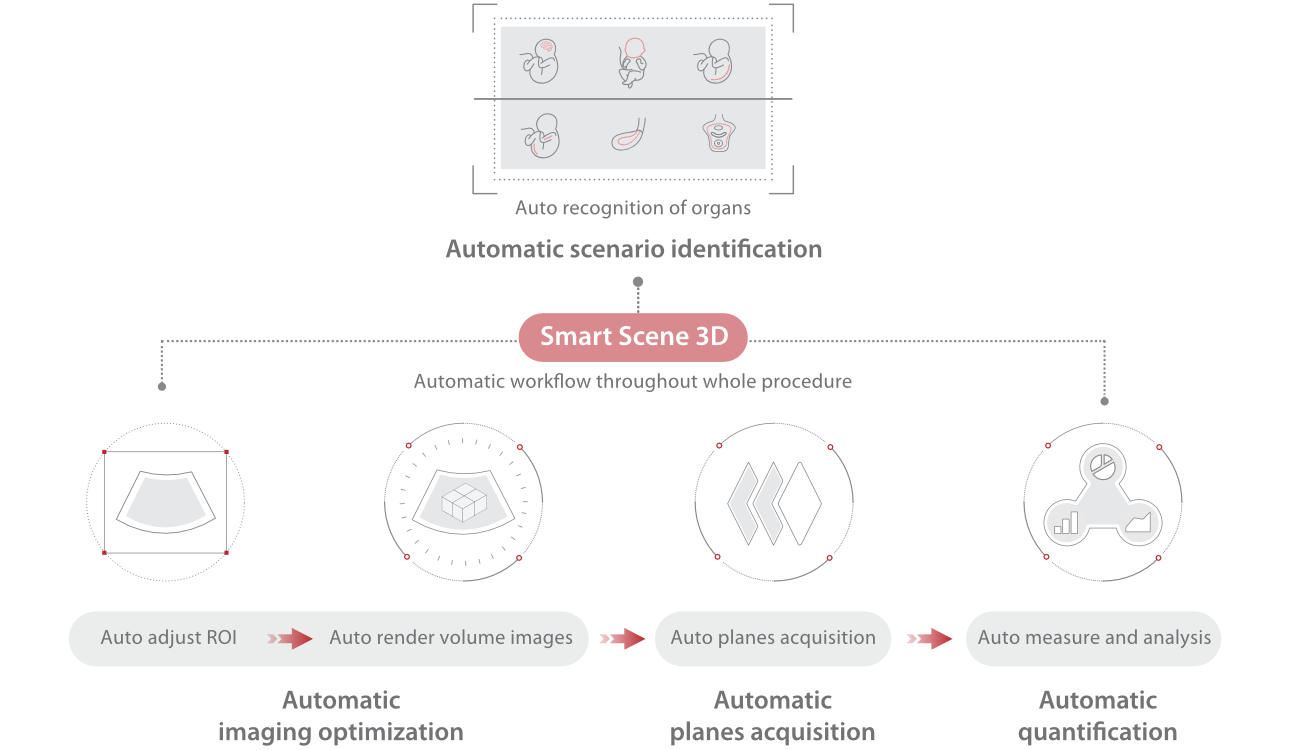

Nuewa I9, dirancang secara khusus untuk perawatan kesehatan wanita dan bayi baru lahir, menghadirkan pengalaman yang inovatif. Inovasi ini dikembangkan berdasarkan wawasan mendalam atas skenario klinis yang kompleks, memberikan jawaban yang akurat dan tepat waktu serta efisiensi dan pengalaman pengguna yang luar biasa.

Platform ZST+ merupakan inovasi luar biasa yang mewakili evolusi ultrasound. Mentransformasikan metrik ultrasound dari pembentukan cahaya konvensional menjadi pemrosesan berbasis channel data. Mengatasi batasan kompromi tradisional antara resolusi spasial, resolusi temporal, dan keseragaman jaringan, menghadirkan mutu gambar yang luar biasa untuk solusi pencitraan tak terbatas dengan peningkatan secara berkelanjutan.